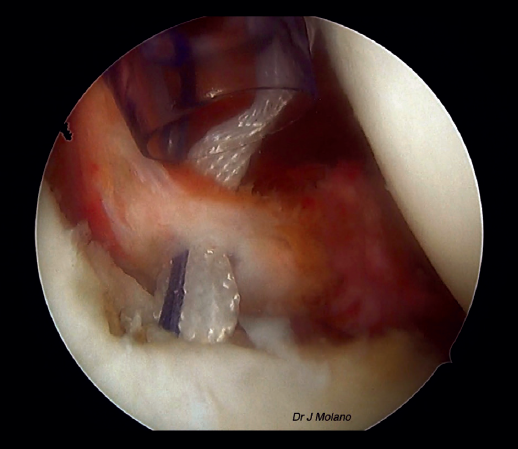

Figura 6. Visión artroscópica desde el portal posterior de la ligamentoplastia en hombro derecho previa a la reparación capsulolabral.

Tras ello, se cambia nuevamente la visión al portal posterior y se empieza con la preparación glenoidea de la ligamentoplastia de hombro. Se coloca con motor una aguja de Kirschner de 2,2 mm de diámetro a las 3 horas (hombro derecho) o 9 horas (hombro izquierdo), utilizando como guía la de PushLock® (Arthrex, Naples, FL, USA). Sobre ella se realiza un túnel de 4,5 × 20 mm con broca canulada de 4,5 mm. Posteriormente, se fija el ligamento AchilloCord PLUS® (Xiros, Leeds, UK) en la cara anterior de la glena mediante un tornillo interferencial de tenodesis de tipo Peek® de 4,75 × 15 mm (Arthrex, Naples, FL, USA). Se mantiene en el portal anterior, pero por fuera de la cánula, el ligamento y se continúa con la reparación de Bankart. Habitualmente, en nuestro centro se realiza con 2 anclajes de tipo Iconix® de 1,4 mm, de tipo todo hilo, por debajo de la implantación del ligamento y 1 o 2 por encima que pueden ser Iconix® o PushLock®.